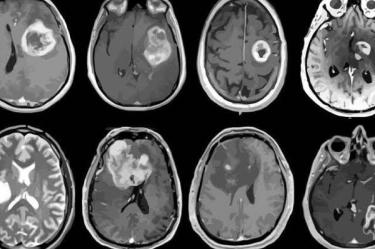

Una niña de 10 años, ciudadana estadunidense, quedó sin acceso a su tratamiento para cáncer cerebral luego de que su familia fuera detenida y deportada a México mientras viajaban a Houston en busca de atención médica. Sus padres y cuatro hermanos también fueron expulsados, dejando a la menor sin cuidados esenciales.

El pasado 4 de febrero, la niña, que aún lucha contra los efectos de una cirugía para extirpar un tumor, fue detenida junto a su familia en un puesto de control migratorio.

Antes de la detención, la niña tomaba medicación para prevenir convulsiones, necesarias tras su cirugía. Ahora, en México, ha quedado sin atención médica adecuada.